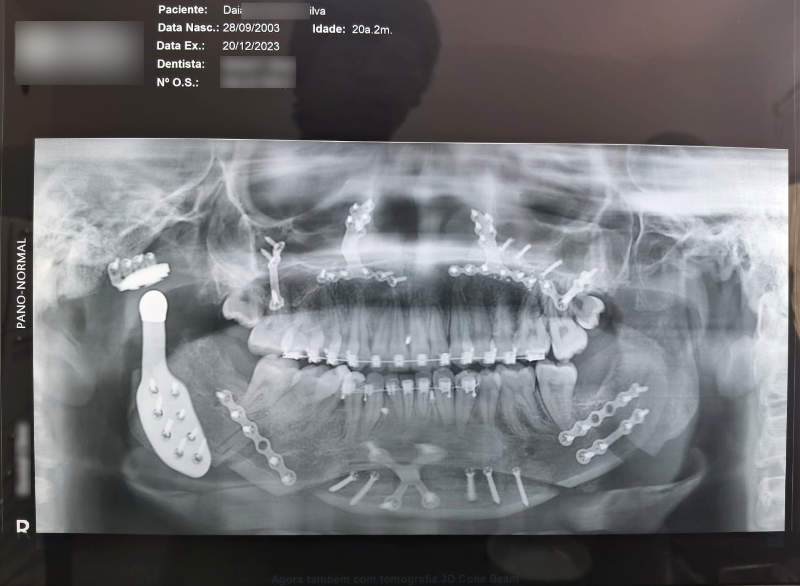

Com uma micro-serra são realizadas osteotomias (cortes) nos ossos para que eles possam ser mobilizados e posicionados adequadamente. Através de medidas realizadas previamente, os ossos são colocados na posição adequada e, por fim, fixados com placas e parafusos de titânio (são biocompatíveis e não provocam rejeição).

As mini-placas permitem uma fixação rígida dos ossos, o que dispensa o bloqueio maxilo-mandibular no pós-operatório ( boca travada).